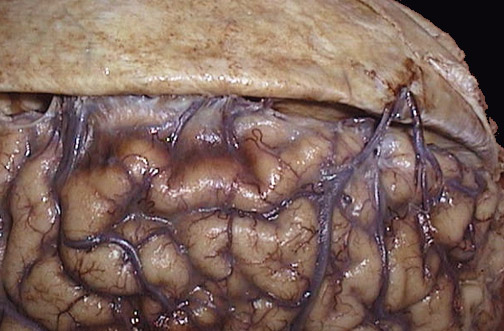

![]() | The dura has been reflected above to reveal the bridging veins that extend across to the superior aspect of the cerebral hemispheres. These can be torn with trauma, particularly if there is significant cerebral atrophy that exposes these veins even more. |